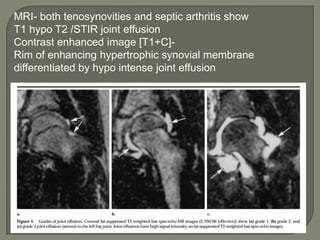

MRI- both tenosynovities and septic arthritis show

T1 hypo T2 /STIR joint effusion

Contrast enhanced image [T1+C]-

Rim of enhancing hypertrophic synovial membrane

differentiated by hypo intense joint effusion

MRI-

1]septic arthritis show signal intensity alteration in the

bone marrow of affected hip joint

2] In transient synovities cases show no such altered

signal entity in bone marrow

T1- poorly defined low signal intesity

T2-/STIR: hyperintese

Contrast study : show enhancment